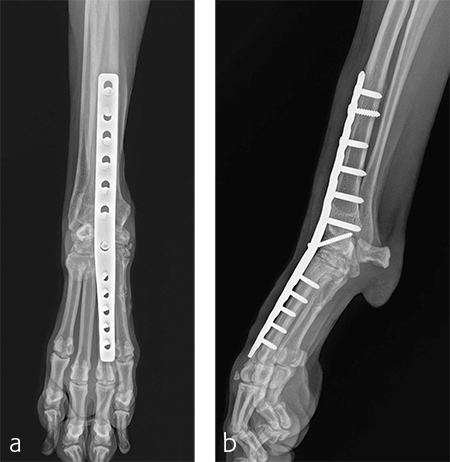

A custom fiberglass palmar splint was applied from the paw to just distal to the elbow after surgery. The splint was used for 4 weeks followed by a soft padded bandage for 4 weeks. Bandage changes were performed weekly. Activity was restricted to leash walks only for 12 weeks postoperatively. Radiographic examination 8 weeks after surgery revealed early healing of the pancarpal arthrodesis and stable implants. No complications were noted (Fig 6).

Immediate postoperative images confirmed anatomic alignment and adequate carpal extension (Fig 10). At the 11-week postoperative follow-up examination, functional recovery was very good with images revealing stable implants and healing of the arthrodesis (Fig 11). The dog was then allowed to return to normal activity.